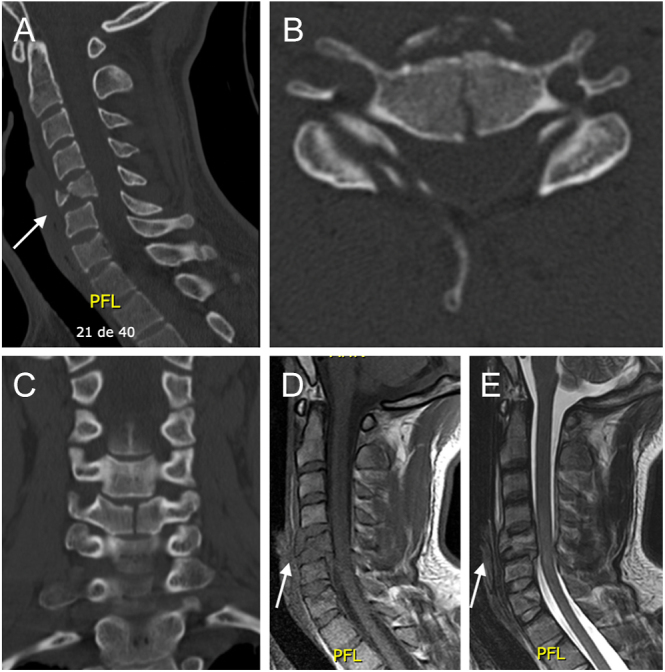

颈椎泪滴骨折的特征是位于椎体前下角的三角形碎片。屈曲型泪滴骨折是由屈曲-压缩机制引起的高度不稳定损伤。这些损伤的一个显著特征是椎体后滑脱,这通常与神经系统损伤的高风险相关。前路入路是屈曲型泪滴骨折最常用的手术治疗方法。相反,伸展型泪滴骨折主要影响椎体轴,通常是稳定的损伤,可以非手术治疗。

Teardrop fractures of the cervical spine are characterized by a triangular-shaped fragment located in the anteroinferior corner of the vertebral body. Flexion-type teardrop fractures are highly unstable injuries resulting from a flexion-compression mechanism. A notable feature of these injuries is retrolisthesis of the vertebral body, which is often associated with a high risk of neurological compromise. The anterior approach is the most commonly used surgical treatment for flexion-type teardrop fractures. In contrast, extension-type teardrop fractures primarily affect the axis vertebral body and are generally stable injuries that can be treated nonoperatively.